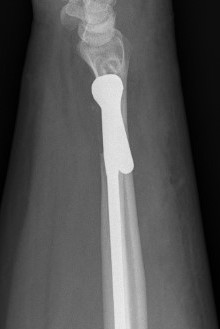

DRUJ Replacement